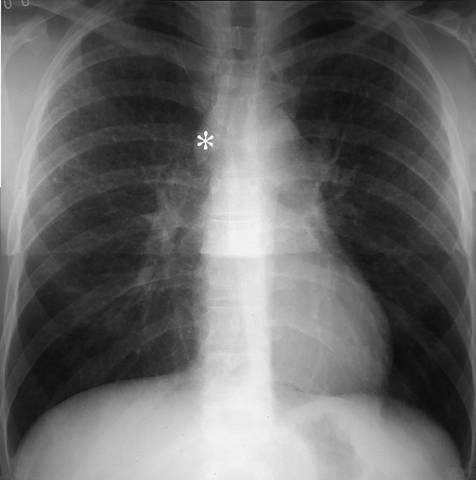

Sarcoidosis with enlarged lymph nodes in chest x-ray (PA view). Peripheral hilar lymph nodes are bilaterally enlarged. In addition, the azygos lymph node (*) is large. For lateral view, see Sarcoidosis with Enlarged Lymph Nodes in Chest x-Ray (Lateral View).